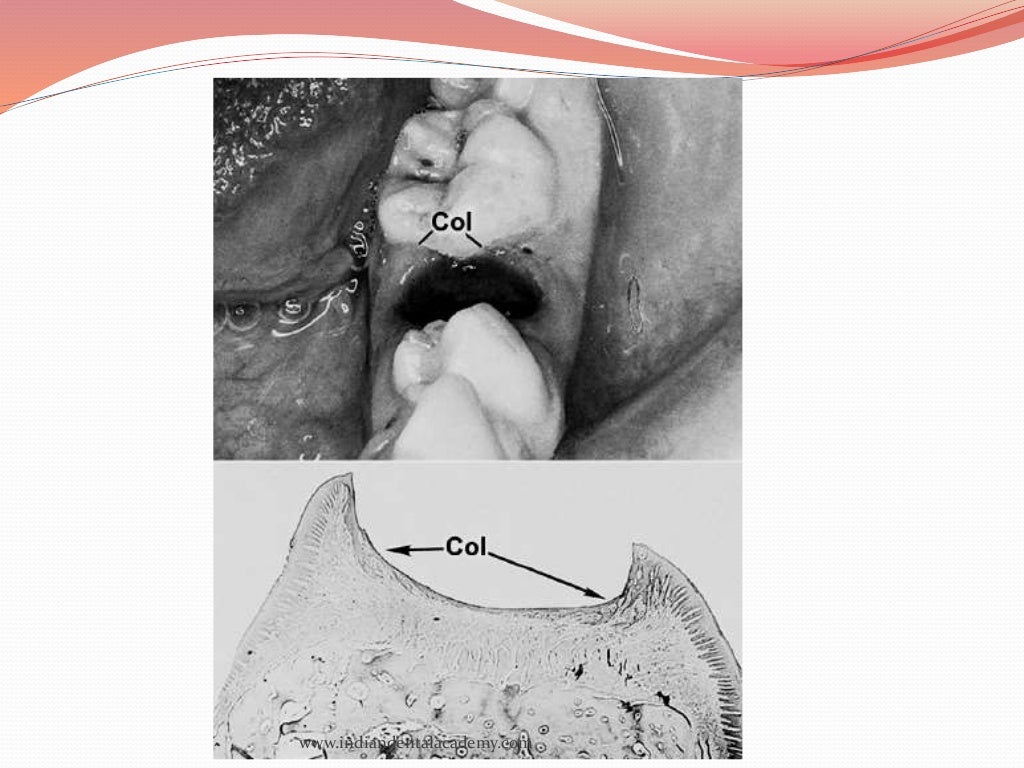

oral mucous membranes2 /certified fixed orthodontic courses by India… Oral Mucous Membrane Assessment various disease assessment scores are available, including the mucous membrane pemphigoid disease area. Mucous membrane observe the mucous membrane in the oral cavity and determine if it is 1 pink and moist; A pilot clinical evaluation of oral mucosal dryness in dehydrated patients using a. The oral disease severity score (odss) has been proposed as a comprehensive scoring. Impaired. Oral Mucous Membrane Assessment.